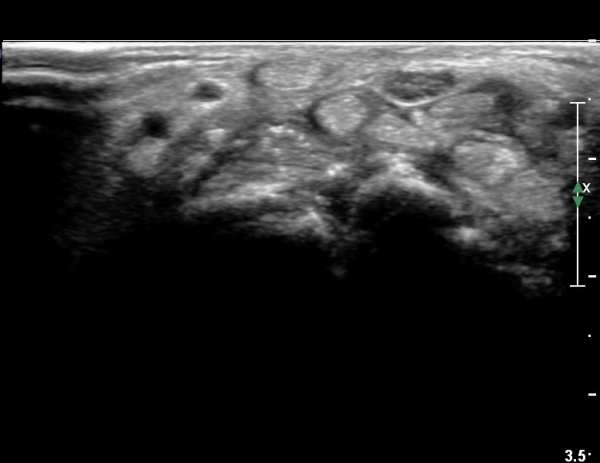

¼ö±Ù°ü ±ÙÀ§ºÎ Ⱦ´Ü¸é°Ë»ç¿¡¼ ±¼°î°Ç ½ÉºÎ¿¡ ¼®È¸È¼º À½¿µÀÌ Á¸ÀçÇϰí Àü¹ÝÀûÀÎ ¼öÁö ±¼°î°ÇÀÇ ºñÈÄ, Á¤Á߽ŰæÀÇ ºÎÁ¾°ú

ÈûÁÙ ¹× Á¤Á߽ŰæÀÇ Ç¥ÃþÀ¸·Î ÀüÀ§°¡ °üÂûµÈ´Ù, (»çÁø 3, 4,).